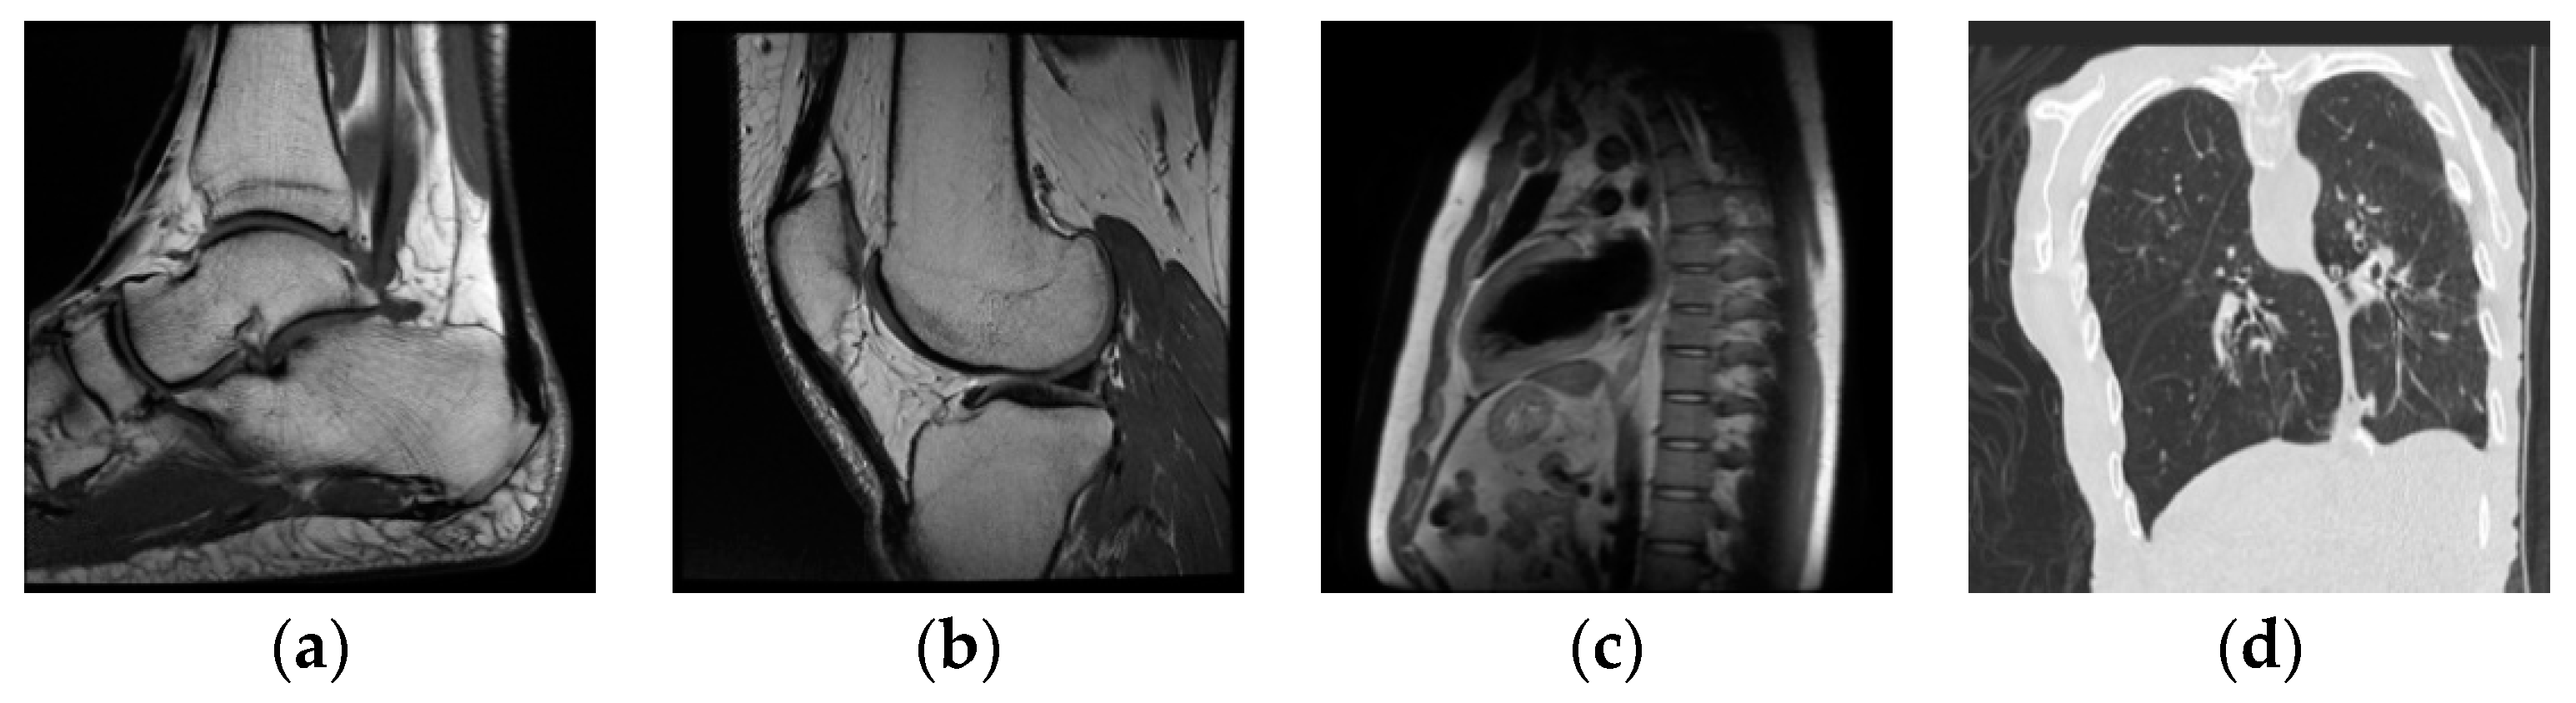

| The scheme | Integrity verification | Tamper localization |

| Ali Al-Haj [8] | Yes | No |

| Hua [9] | No | No |

| A. Kanso [10] | No | No |

| Chong Fu [11] | No | No |

| J.B. Lima [12] | No | No |

| Ping [28] | No | No |

| Proposed scheme | Yes | Yes |

| The scheme | Integrity verification | Tamper localization | Error in image recovery (ROI) |

| Priyanka [19] | No | No | / |

| Zhang [20] | No | No | No |

| Priyanka [21] | No | No | Yes |

| Wu [22] | No | No | No |

| Sangita [24] | No | No | Yes |

| Xiang [25] | No | No | No |

| Ping [28] | No | No | No |

| Liu [29] | No | No | No |

| Proposed scheme | Yes | Yes | No |